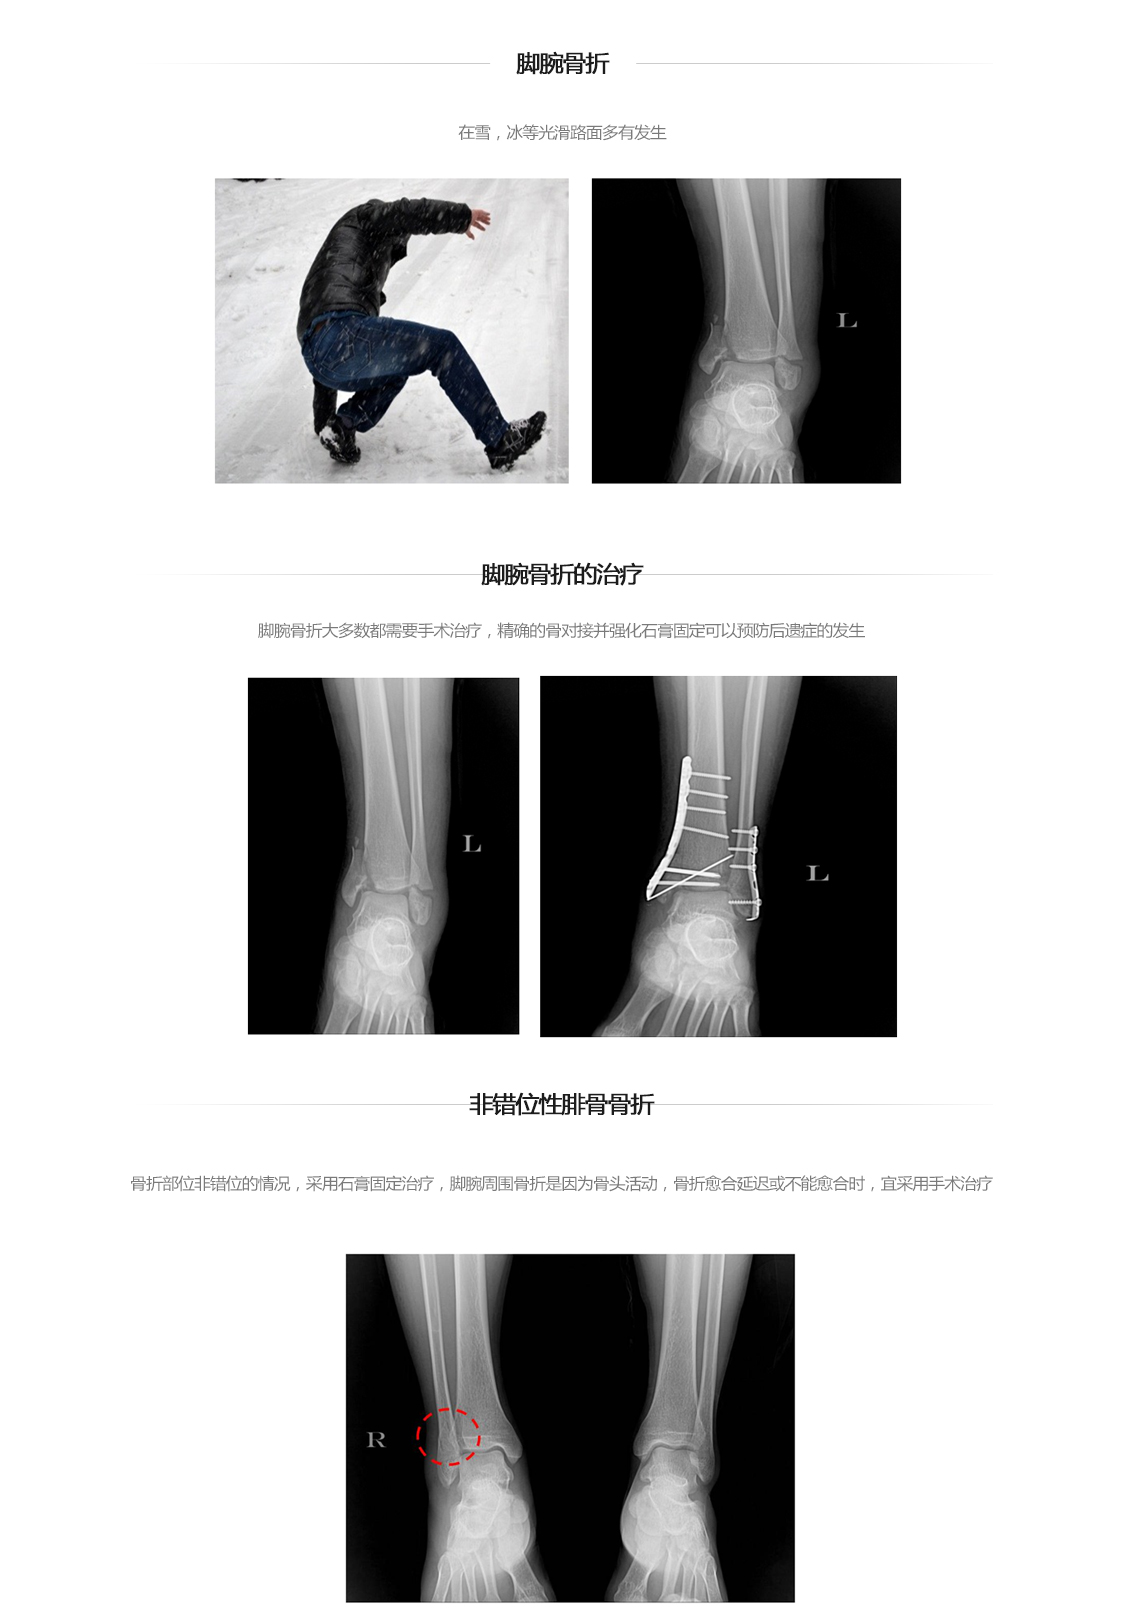

脚腕关节骨折

脚腕骨折